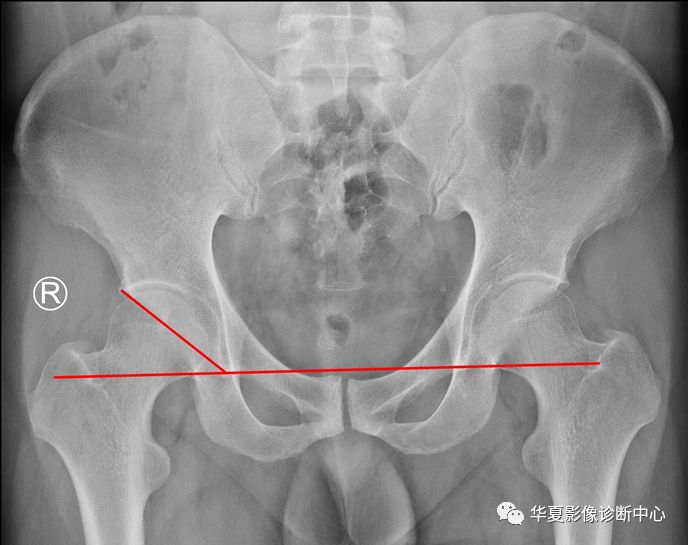

7、Perkin方格:骨盆正位片,经过双侧髋臼Y形软骨中心画水平线,再通过两侧髋臼外上缘引其垂线,两侧髋关节被分为四个区域,正常时,股骨头骨骺中心位于内下区域,髋关节发育性脱位时,股骨头骨骺位于外上区域。